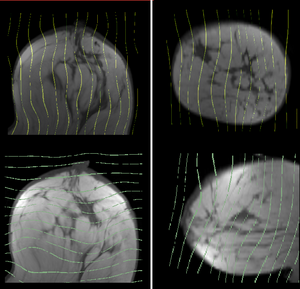

Registration Results

unregistered unregistered

affine registered affine

Bspline registered BSpline 9x9x4 max 15mm

Bspline registered Deformation field for BSpline 9x9x4 max 10mm

Bspline registered BSpline 7x7x5 max 10mm

After N4 bias correction and histogram equalization:

Bspline1 deformation only Deformation of Post image from unmasked BSpline 7x7x5 max 10mm

Bspline registered + tumor mask BSpline 7x7x5 max 10mm + tumor mask

Bspline1 deformation only Deformation of Post image from masked BSpline 7x7x5 max 10mm